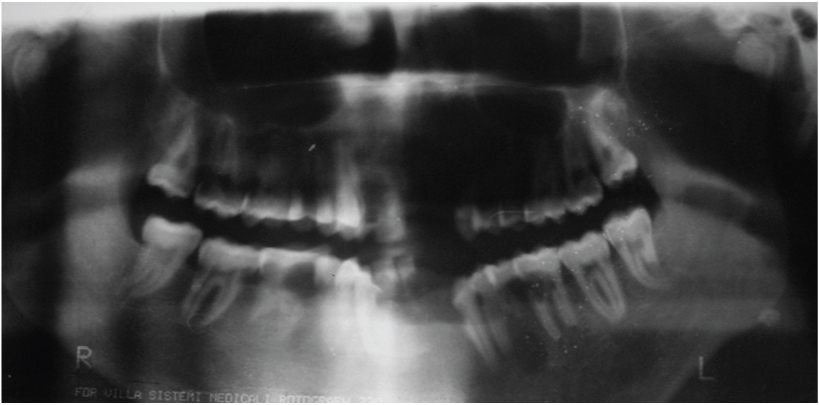

[Table/Fig-3] showing the normal morphology of crowns of the maxillary teeth. [Table/Fig-4] showing the normal morphology of crowns of the mandibular teeth. Full mouth intraoral periapical radiograph revealed complete root resorption in relation to 11, 12, 41 and 42; cervical resorption in 15, 33, 34 and 43, 44; apical resorption in 16, 24, 25 and 26. Resorption in both apical and cervical region was noticed in relation to 35, 36 and 46. Panoramic radiographs showed multiple ill defined radiolucent areas in apical third and cervical region of all teeth in varying degree. Lateral view of skull showed no evidence of any skull changes. In [Table/Fig-5] intraoral periapical radiograph showing complete root resorption in relation to 11 and 12. In [Table/Fig-6] intraoral periapical radiograph showing complete root resorption in relation to 41 and 42. In [Table/Fig-7] intraoral periapical radiograph showing cervical resorbtion in relation to 15 and apical root resorption of mesial and distal roots in relation to 16. Loss of PDL space in 17 can be appreciated.

In [Table/Fig-8] intraoral periapical radiograph showing cervical resorption in relation to 33, 34, resorption in both cervical and apical region in relation to 35, 36. In [Table/Fig-9] intraoral periapical radiograph showing cervical and apical resorption in relation to 24, 25 and apical resorption in relation to 26. In [Table/Fig-10] intraoral periapical radiograph showing cervical and apical resorption in relation to 35, 36 and apical resorption in relation to 37. In [Table/Fig-11] intraoral periapical radiograph showing cervical and apical resorption in relation to 46, 47 and 48. In [Table/Fig-12] intraoral periapical radiograph showing cervical resorption in relation to 43, 44 and 45. [Table/Fig-13] Orthopantomograph. In [Table/Fig-14] lateral view of skull showing no osteogenic changes. In [Table/Fig-15] histological examination of extracted mobile teeth showing striae of Retzius, dentinal tubules and interglobular dentin with an area resembling dead tract. Correlating the history, clinical findings supported by radiographic appearance, diagnosis of Multiple Idiopathic external root resorption was made.